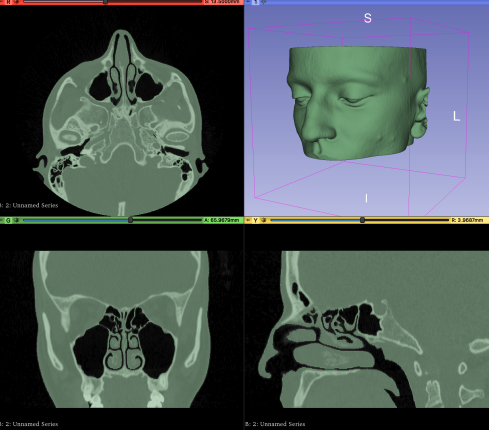

A major focus of my current work is applying these methods to aerodynamic defect detection in airfoils and the identification of pathologies in human upper airways extracted from CT Scans, bridging engineering and medical applications.

ML-based Diagnosis of Nasal Breathing Difficulties Aided by CFD

Politecnico di Milano – Computational Geometry & Machine Learning

Development of a pipeline for the automatic diagnosis of nasal breathing disorders using CFD simulations and ML models.

Based on patient-specific anatomical geometries and Computational Geometry methods for automation and data augmentation.

• Thesis: A Computational Geometry approach for Machine Learning–based diagnosis of nasal breathing difficulties aided by CFD.